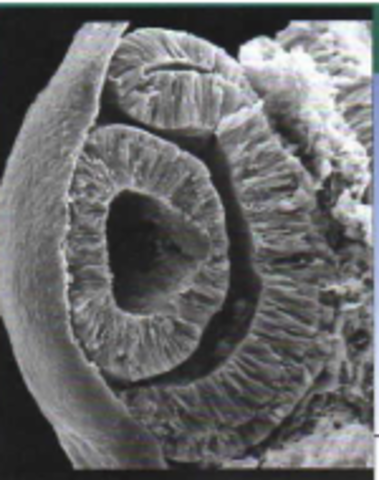

Semana 4: Formación de vesículas ópticas y laminas de cristalinos

• Semana 5: Desarrollo de la excavación papilar y de la vesícula del cristalino

Semana 5: Desarrollo de la excavación papilar y de la vesícula del cristalino

La vesícula del cristalino pierde el contacto con el ectodermo superficial y se deposita en la boca de la cúpula óptica.